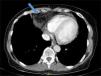

In view of the results of the chest X-ray, an abdominal, pelvic and thoracic CT scan was requested (Fig. 2), which revealed the presence of a Morgagni hernia with visceral fat content and fluid through the hernia orifice. The herniation was causing linear atelectasis at the level of the middle lobe, with no evidence of hilar/mediastinal or axillary lymphadenopathy of significant size or appearance. With the results of the CT scan, a peritoneogram was requested, which ruled out peritoneal fluid leak or pleuroperitoneal communication. The patient was evaluated by general surgery and, given the associated symptoms, the potential complications and the intention to maintain long-term renal replacement therapy with PD, she underwent surgical closure of the hernia defect. Following the surgery, she was temporarily put on haemodialysis. One month after the intervention, and in the absence of associated complications, the patient restarted PD therapy with an overnight exchange. She has gradually been losing residual renal function, for which it has been necessary to increase to 3 daily exchanges, with no complications or new hernias.